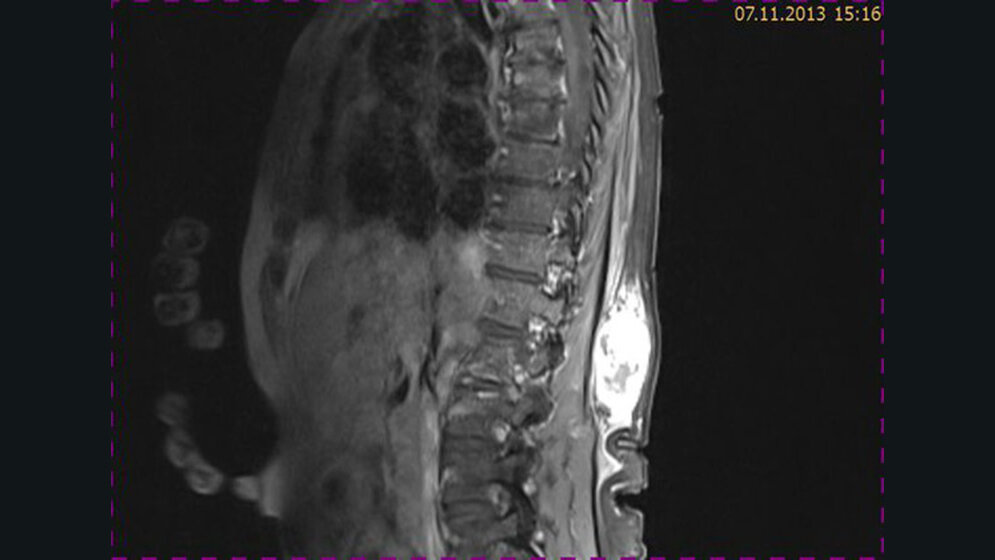

Tumoröse Veränderungen: Fibrosarkom

Schnittbilddiagnostik der Wirbelsäule (4.20)

Primäre Malignome der Wirbelsäule machen weniger als 5 % der primären Knochentumoren aus. Fibrosarkome des paravertebralen Bereiches sind seltene Lokalisationen dieser Entität.

Primäre Malignome der Wirbelsäule machen weniger als 5 % der primären Knochentumoren aus. Fibrosarkome des paravertebralen Bereiches sind seltene Lokalisationen dieser Entität. Sie haben ein hohes Malignitätspotenzial bezüglich der Rezidiv-, Metastasierungs- und der Mortalitätsrate.